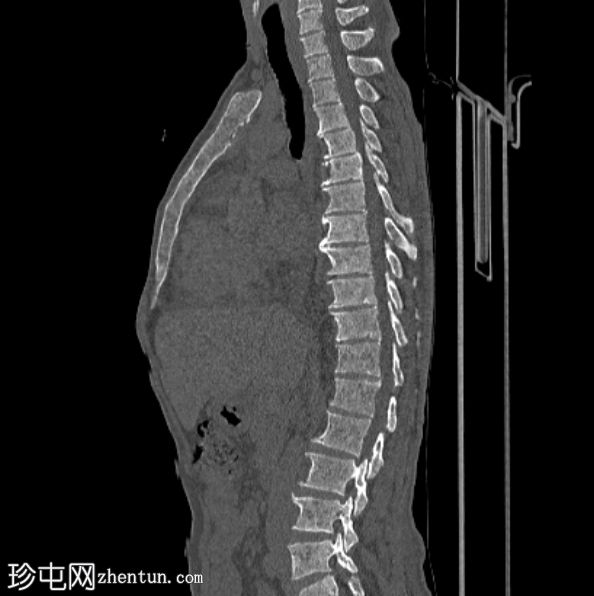

矢状位

骨窗

6.jpg

弥漫性骨硬化,FDG摄取轻度增高

骨硬化